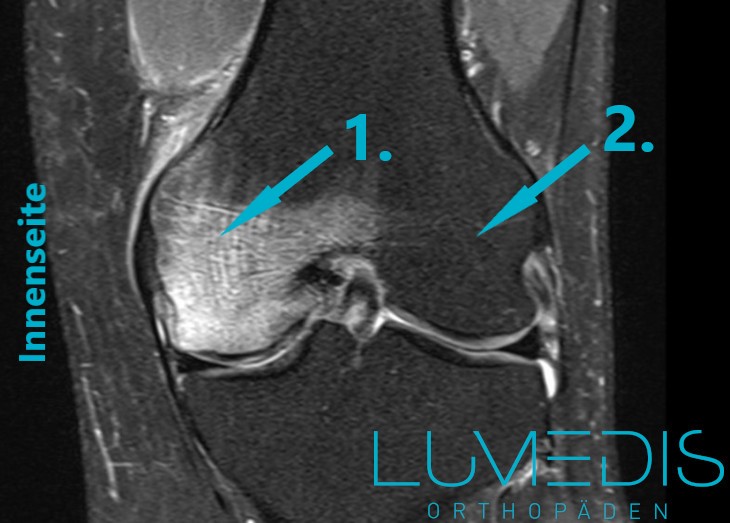

MRT eines Bone bruise an der medialen Femurkondyle

MRT eines Morbus Ahlbäck der medialen Femurkondyle (Innenrolle im Knie)